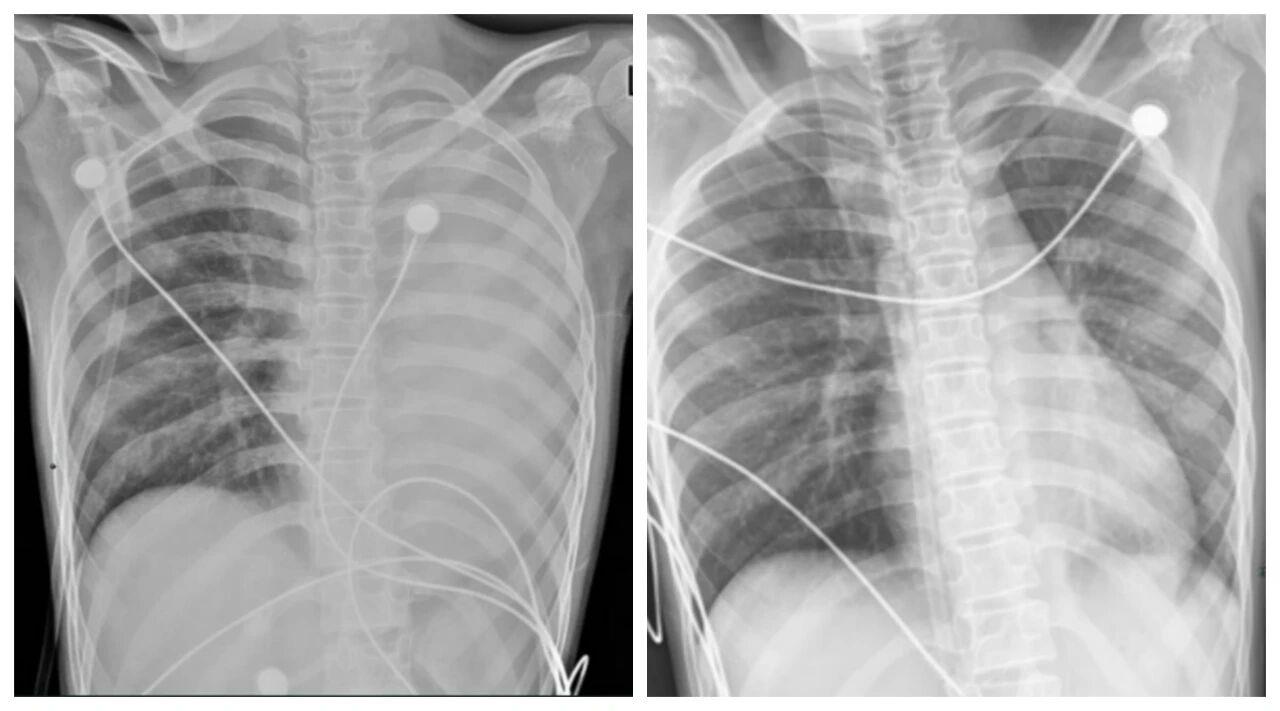

△笑笑治疗前,左肺呈“白肺”状态,治疗后“白肺”被吸收,心脏边缘清晰可见。图源:浙大四院

一开始,她只是轻微咳嗽,发热后在外院检查提示肺炎、肺不张,转诊到浙大四院儿科时,笑笑出现呼吸急促、胸闷胸痛,血氧饱和度勉强维持在90%左右,胸片显示左肺已完全呈“白肺”改变,病情急剧恶化。